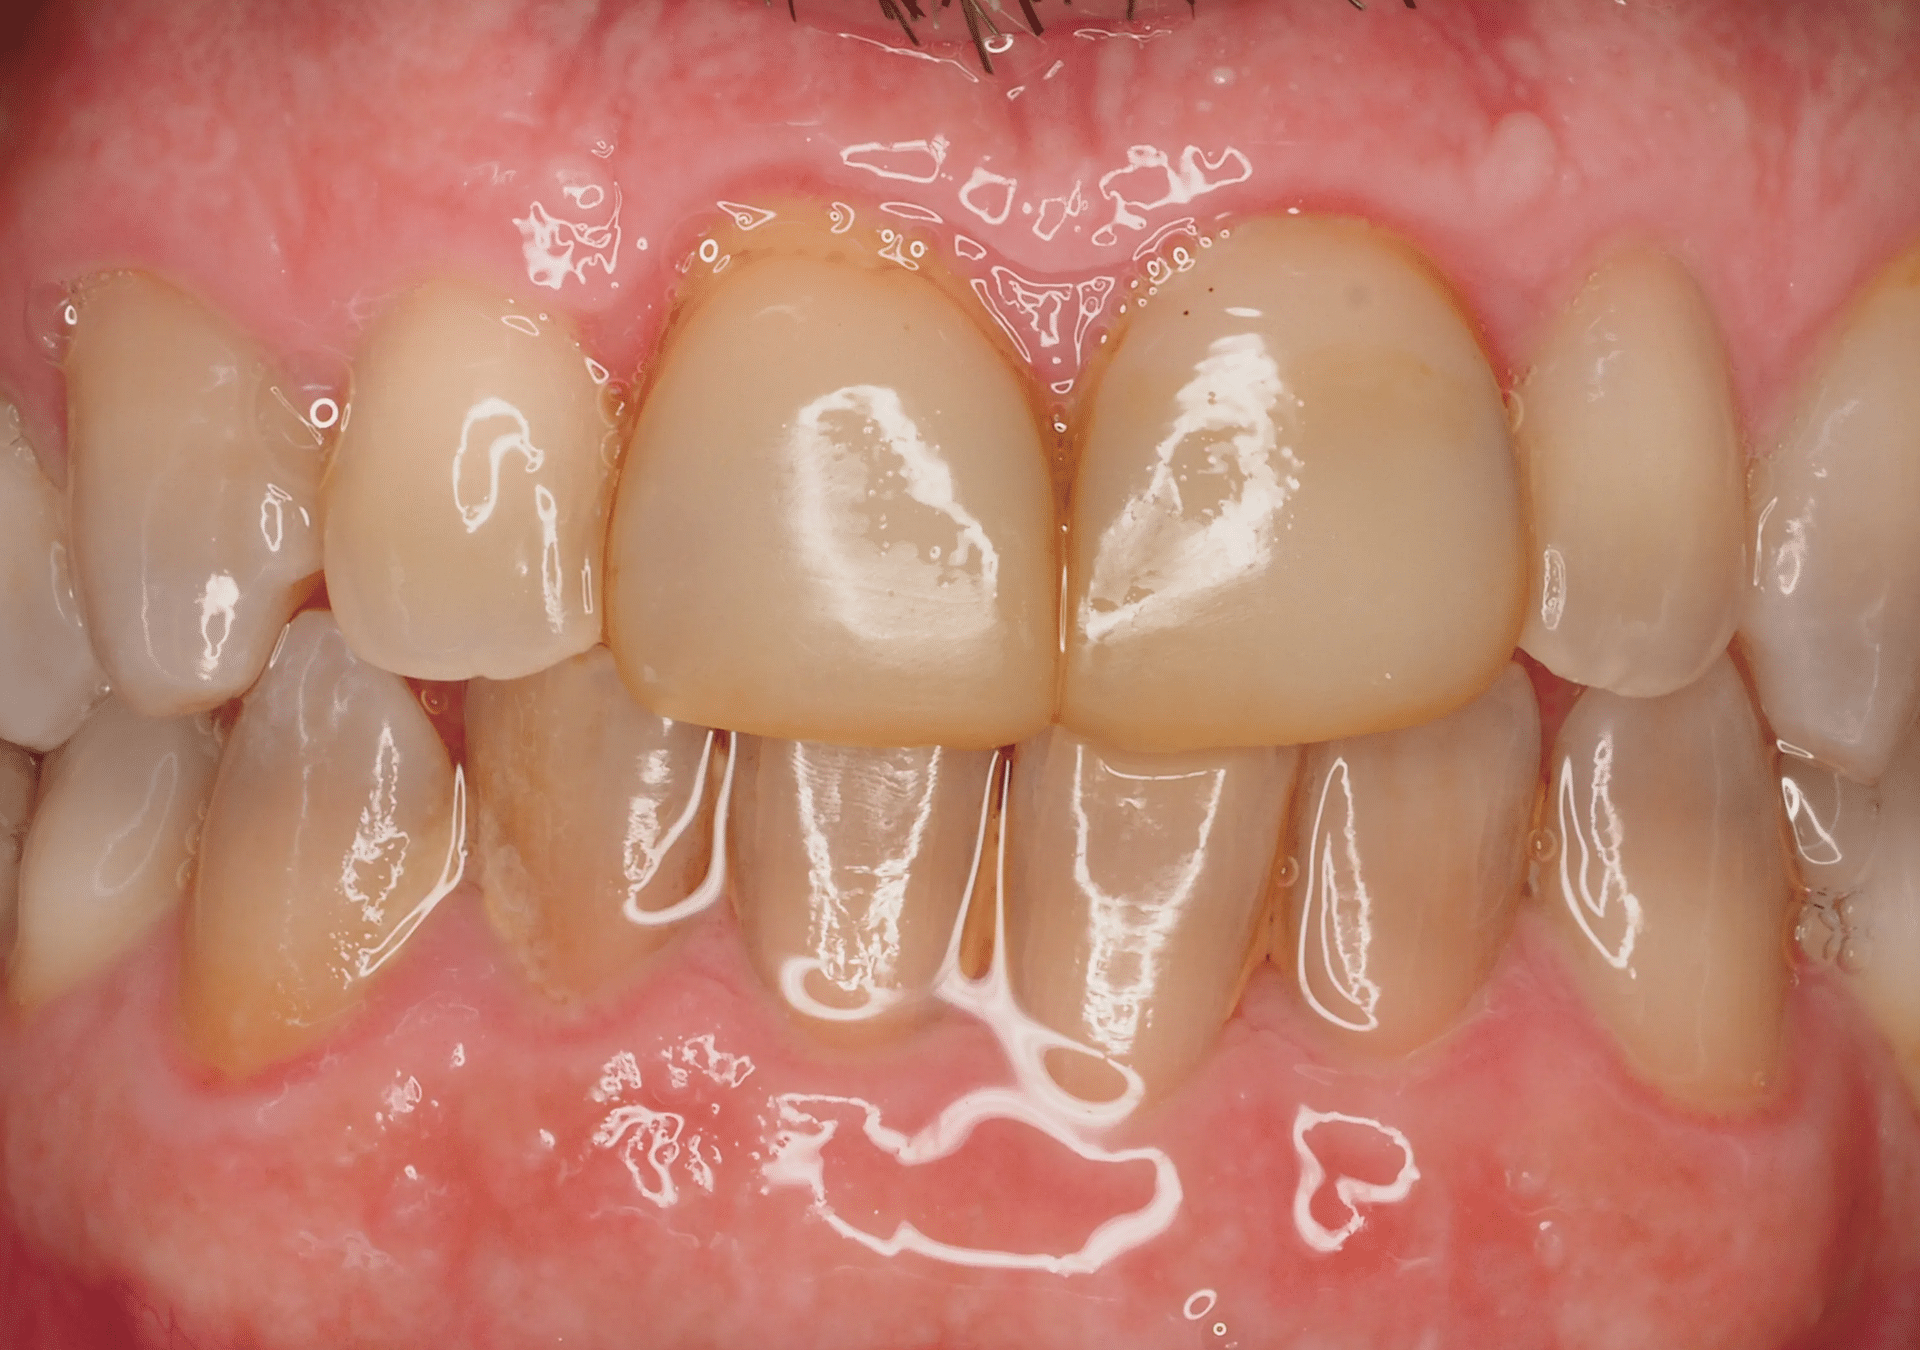

- 25 años de experiencia en restauraciones de resina de composite tanto en sectores anteriores como posteriores.

- Técnicas de aislamiento para garantizar la longevidad y la integridad de la restauración.

- Resultados estéticos comparables a la cerámica, de larga durabilidad.